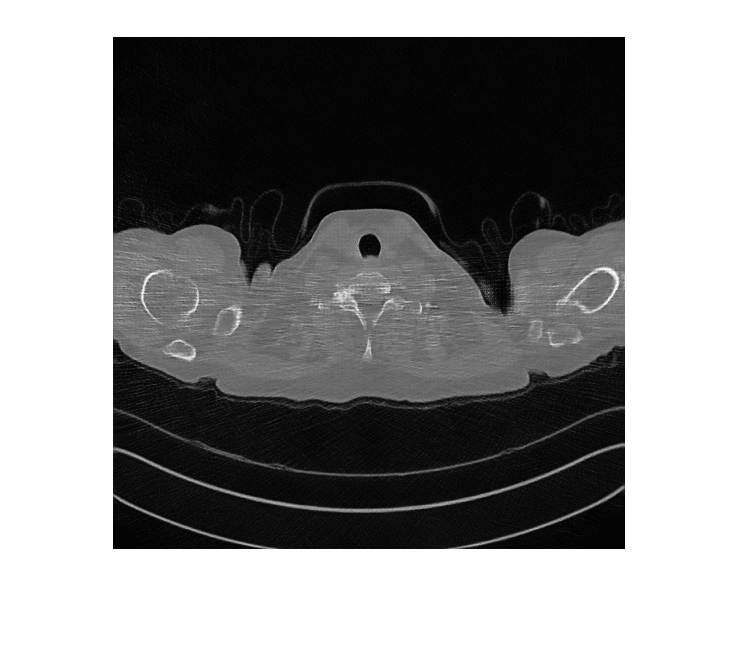

FileExtensions=exts,ReadFcn=readFcn);Предварительно просмотрите учебное изображение от низкой дозы и обучающих наборов данных CT большей дозы.

montage({lowDose,highDose})

Отобразите входной CT низкой дозы, сгенерированную версию большей дозы и изображение большей дозы основной истины в монтаже. Несмотря на то, что сеть обучена на данных из одного терпеливого скана, сеть делает вывод хорошо, чтобы протестировать изображения от других терпеливых сканов.

imshow([imLowDoseTest imHighDoseGenerated imHighDoseGroundTruth]) title(['Low-dose Test Image ',num2str(idxToTest),' with Generated High-dose Image and Ground Truth High-dose Image'])